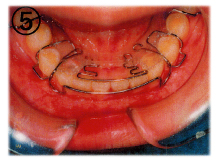

当医院では「床(しょう)矯正」という矯正治療を実践しております。

基本的には永久歯を抜かず、顎を拡げて歯を並べる治療の事です。

床矯正で使用する装置は簡単に取り外せるので、虫歯や歯周病を患いにくく、清潔な口腔環境が保てます。